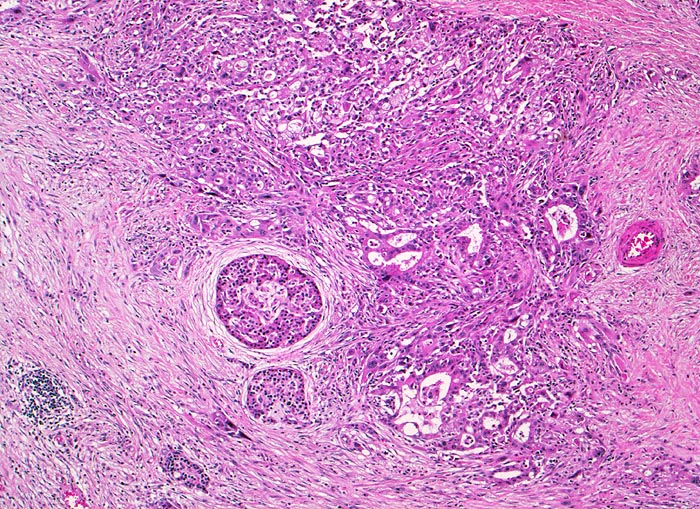

Die meisten Pankreaskarzinome sind mässig bis hoch differenziert und führen zu einer deutlichen desmoplastischen Stromareaktion (derbe Konsistenz). Hochdifferenzierte Tumoren (> 1502) können sehr ähnlich aussehen wie eine chronische Pankreatitis (> 4243). Im Gegensatz zur Pankreatitis sind die neoplastischen Drüsen verformt oder rupturiert und zeigen zelluläre Atypien (grosse polymorphe Kerne mit prominenten Nucleolen). Die Tumordrüsen sind unregelmässig im Stroma angeordnet und nicht lobulär wie in der Pankreatitis. Nicht selten ist eine Nervenscheideninvasion nachweisbar (> 5884). Gelegentlich zeigen die Gänge im tumorfreien Parenchym dysplastische Veränderungen oder der Tumor breitet sich intraduktal entlang des Pankreasganges aus.

• Unregelmässige Anordnung der Drüsen (keine Läppchenarchitektur erkennbar).

• Desmoplastisches Stroma.

• Rechts oben Reste von nicht neoplastischem Pankreasparenchym mit fokaler chronisch obstruktiver Pankreatitis als Folge von tumorbedingten Gangobstruktionen: Vollständige Atrophie des exokrinen Pankreas bei erhaltenen Inseln. Ersatz des atrophen Parenchyms durch Fibrose. Chronisches Entzündungsinfiltrat.